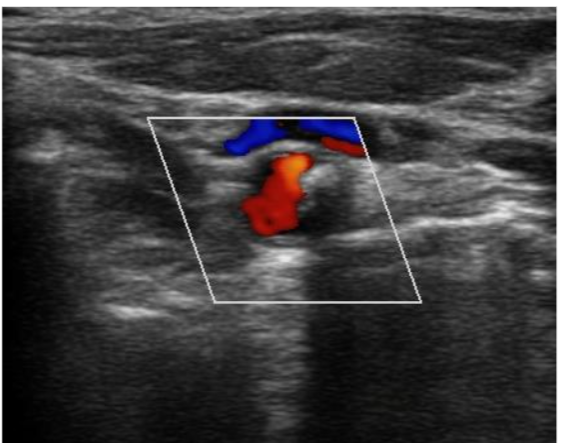

Carotid Arteries

Using ultrasound is a technique that can be used pre- and postoperatively to assess blood flow and vascular status in the central veins to help guide fluid management. In this situation, following the central venous catheterization, the use of a Doppler ultrasound can be beneficial.

Inferior Vena Cava

Venous excess ultrasound (VeXUS) is a technique that can be used pre- and postoperatively to assess blood flow and vascular status in the central veins to help guide fluid management. In this situation, following the central venous catheterization, the use of a Doppler ultrasound can be beneficial.